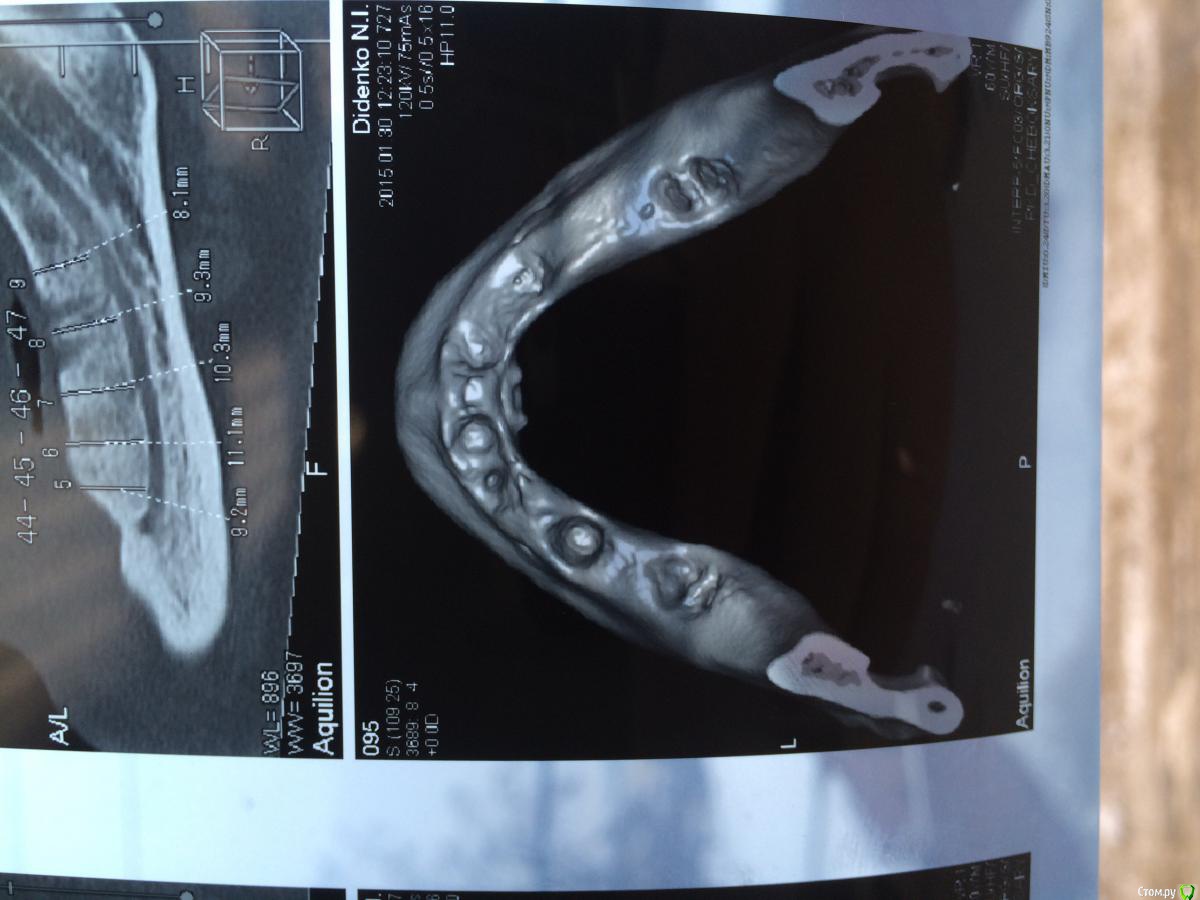

urseva19.05.10 Опубликовано 31 января, 2015 Поделиться Опубликовано 31 января, 2015 Коллеги, в каких позициях на ваш взгляд целесообразнее поставить имплантаты желательно без НКР ( пациент ограничен во времени) что бы в последствии протезироваться съемным протезом на локаторах? На верх не смотрите там все ясно Спасибо! Ссылка на комментарий

Alejandro Опубликовано 31 января, 2015 Поделиться Опубликовано 31 января, 2015 В области 36,46 толщина альвеоляра какая? Ссылка на комментарий

urseva19.05.10 Опубликовано 31 января, 2015 Автор Поделиться Опубликовано 31 января, 2015 10,5 и 9,2 соответственно Ссылка на комментарий

syrovovec Опубликовано 31 января, 2015 Поделиться Опубликовано 31 января, 2015 Ставьте в межментальное 2 или 4, как вам больше нравитсяPs фотки очень неудобно смотреть, срезы замеры не информативные 1 Ссылка на комментарий

Alejandro Опубликовано 31 января, 2015 Поделиться Опубликовано 31 января, 2015 Я бы поставил два межментально в области клыков, и два в области шестёрок тогда. Можно не сильно параллелить - на локаторах это прощается. Ссылка на комментарий

urseva19.05.10 Опубликовано 1 февраля, 2015 Автор Поделиться Опубликовано 1 февраля, 2015 1. выравнивайте гребень2. Позиции 34 , 32, 42, 44, если болты позволяют их субкрестально поставить , то притопите, и ушиться бы двурядно, 1. Всё-таки считаете без НКР не обойтись?2. С 32,42 понятно, а если в области 36,46 установить не будет ли лучше фиксация протеза, да и условия вроде позволяют. Как думаете? Ссылка на комментарий

kriokov Опубликовано 1 февраля, 2015 Поделиться Опубликовано 1 февраля, 2015 1. Всё-таки считаете без НКР не обойтись?2. С 32,42 понятно, а если в области 36,46 установить не будет ли лучше фиксация протеза, да и условия вроде позволяют. Как думаете?1. не знаю, лучше бы просто ОПТГ глянуть и четко срезы в межментальном отделе2. Я не делал так , ставил всегда по просьбе ортопеда в межментальном Ссылка на комментарий

колесников Опубликовано 1 февраля, 2015 Поделиться Опубликовано 1 февраля, 2015 тут подойдёт постановка по типу ,,всё на 4ёх,, ,обходя ментальные.костные пики во фронте надо нивелировать и материал всётаки оставить. Ссылка на комментарий

АнтонТЛТ Опубликовано 9 февраля, 2015 Поделиться Опубликовано 9 февраля, 2015 Потихоньку задумываюсь об этом. В области каких зубов думаете без нкр получиться?ширина достаточная, так что практически в любом месте можно поставить короткие имплантаты Ссылка на комментарий